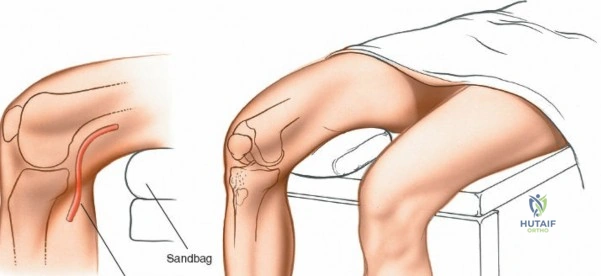

Patient Positioning

The patient is typically placed in a supine position on the operating table.

- Supine Position: Allows for easy access to the medial compartment of the knee.

- Leg Holder or Bolster: For arthroscopic procedures, a well-padded leg holder often secures the thigh, allowing the lower leg to hang freely. Alternatively, a foam bolster beneath the distal femur permits knee flexion while maintaining stability.

- Flexion Capability for Open Approach: As highlighted in the seed content, for an open medial meniscectomy, "Remove the end of the table so that the knee can be flexed beyond a right angle." This maneuver, often aided by an assistant holding the foot, is crucial for gaining optimal visualization and access to the posterior horn of the medial meniscus. Maintaining the knee in hyperflexion while applying a valgus stress and external rotation of the tibia opens the medial compartment and exposes the posterior structures.

- Tourniquet Application: "Exsanguinate the limb by elevating it for 2 to 5 minutes or by applying a soft rubber bandage. Then, inflate a tourniquet." A pneumatic tourniquet is routinely applied to the proximal thigh after limb exsanguination (either by elevation or Esmarch bandage) to ensure a bloodless field, which is particularly important for direct visualization during an open procedure. Tourniquet pressure should be individualized, typically 50-100 mmHg above systolic blood pressure, and closely monitored to limit ischemia time.